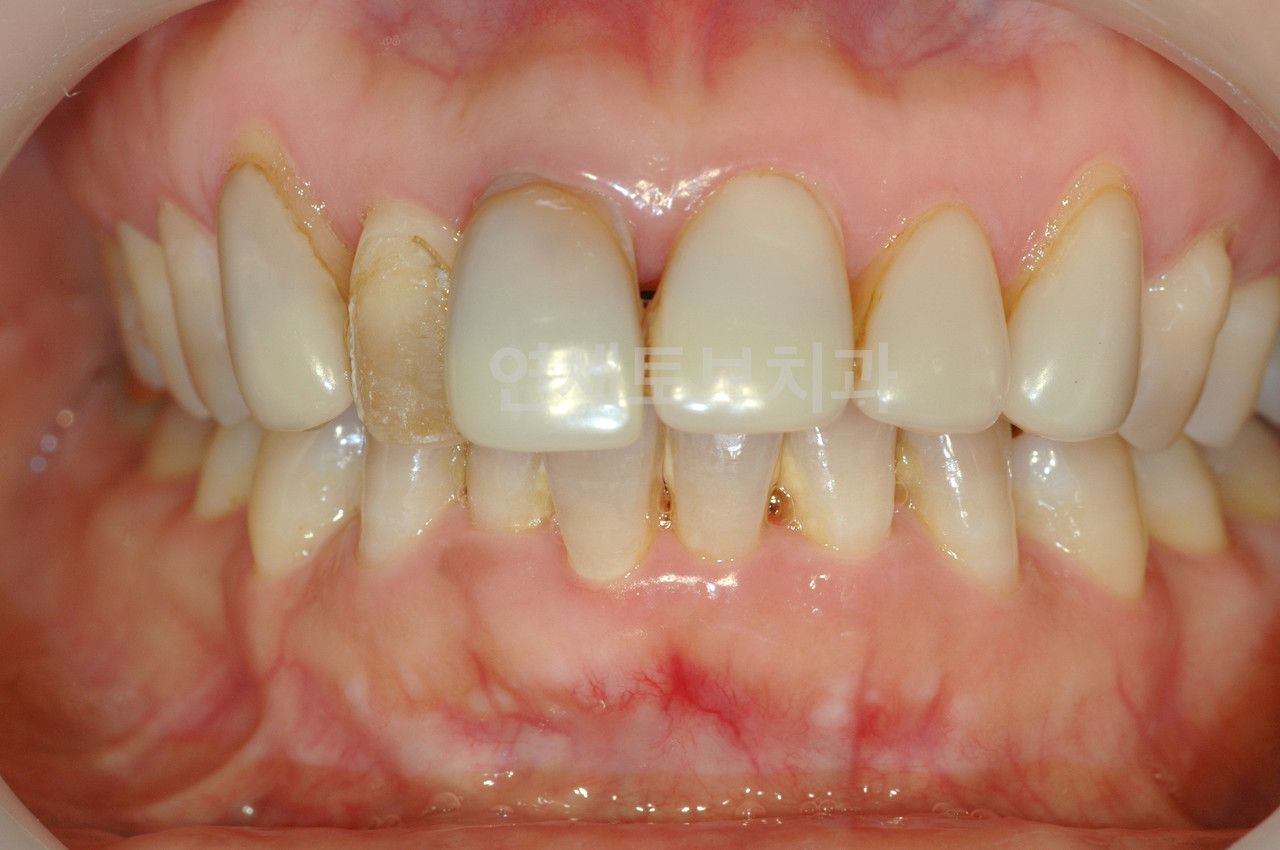

Before

올세라믹 크라운 시술 전

After

올세라믹 크라운 시술 후